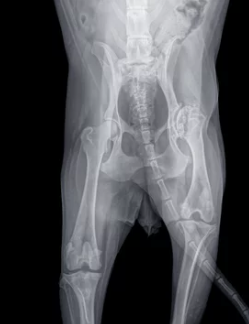

우선 강아지 관절염은 소량의 관절 액체를 채취하여 임상실험 및 방사선 촬영을 활용하여 진단받을 수 있습니다. 또한 X-ray도 관절의 손상도를 알아볼 수 있어 관절염을 진단하는데 도움이 됩니다. 이러한 검진 이전에 평소 생활에서 다음과 같은 행동을 보이면 관절염의 증상으로 의심해 볼 수 있습니다.